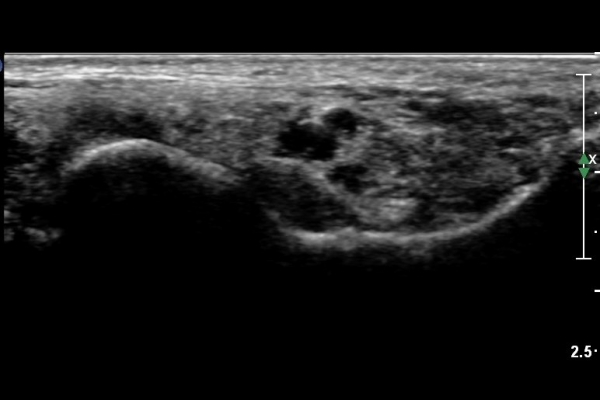

¹ß¸ñÅͳΠȾ´Ü¸é°Ë»ç¿¡¼­ ³»Ãø º¹»ç»À ³»Ãø¿¡ Èİæ°ñ°Ç, ¹ß°¡¶ô±¼°î°Ç°ú ¾öÁö¹ß°¡¶ô±¼°î°Ç

»çÀÌ¿¡¼­ Èİæ°ñ½Å°æÀÌ °üÂûµÇ°í ½Å°æÀÇ Ç¥Ãæ¿¡ µ¿¸Æ°ú Á¤¸ÆµéÀÌ °üÂûµÈ´Ù(»çÁø 1).